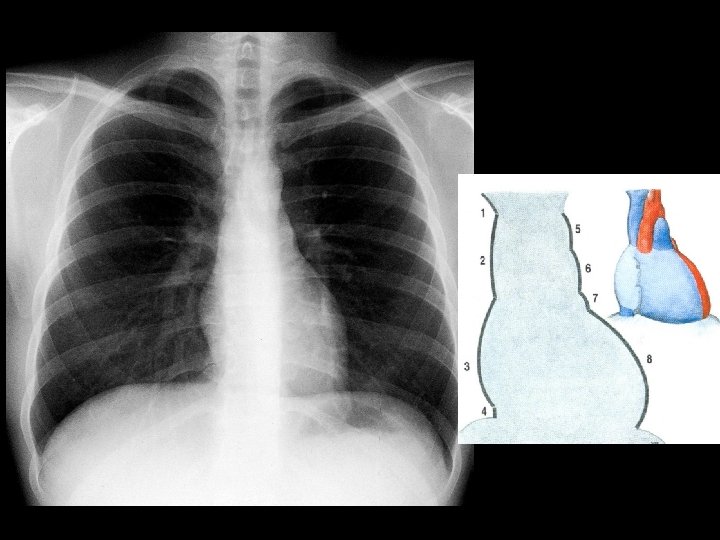

Md - distantia mediodextra 4 - 4, 5 cm Ms - distantia mediosinistra 8 – 9 cm Transverse line of the heart Md + Ms = 15 cm Lg (longitudo) – length of the heart α – inclination of the heart = 45 0 Md Ms α α horizontal line Lg median plane